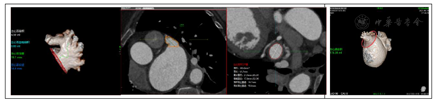

为进一步行评估左心耳结构特点,因此为患者进一步安排CT评估,CT提示左心耳内未见血栓,三维重建后左心耳呈低位,反鸡翅型,开口椭圆形,最短径17.3mm,最长径21.7mm,三维深度19.1mm,二维深度18.0mm,内部梳状肌较为发达。(图1)

阐述该病例处理难点及进一步策略制定:由TEE及CT评估结果可知,该患者左心耳特点①低位心耳,开口较小;②反鸡翅型,且发出转折较早,转折前深度欠缺;因此该患者左心耳封堵难度较大。通过进一步分析左心耳CT后发现,该患者左心耳除主叶外尚有上中下三个分叶,但中下分叶较小且深度较浅,预计输送鞘进入难度及风险均较大,而上叶较宽且深度较中下两个分叶更合适,因此在封堵策略上,考虑采用24mmWatchman封堵器,首选上叶进行尝试(图2)。